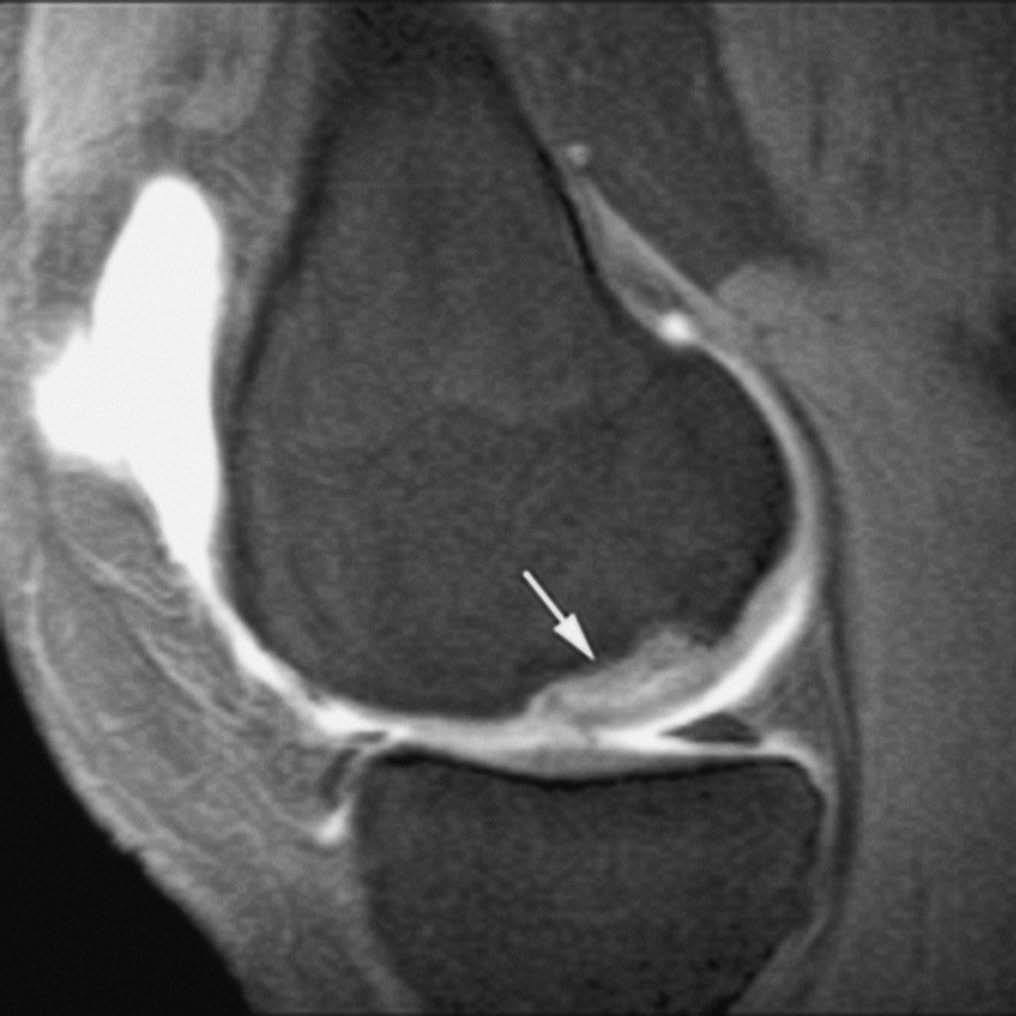

Las LOC son lesiones radiográficamente ocultas en los estadios iniciales. El retraso en el diagnóstico y tratamiento condiciona el desarrollo de importantes secuelas. La RMA es el método diagnóstico de elección; permite realizar un diagnóstico precoz (detectando LOC radiográficamente ocultas), determinar la extensión, estabilidad y viabilidad del fragmento osteocondral (fig. 12), y localizar cuerpos libres articulares1,11,17.

Fig. 12.--Lesión osteocondral estadio 2 en el cóndilo femoral interno de la rodilla. Corte sagital de RMA potenciado en T1 con técnica de supresión grasa que muestra una lesión osteocondral con despegamiento parcial.